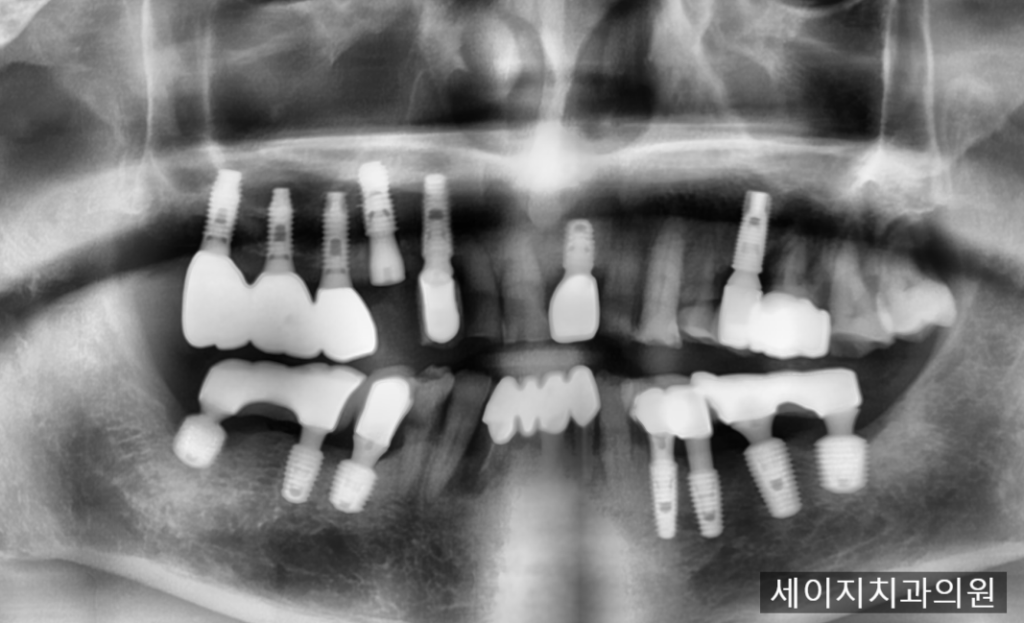

24. 12. 09

임플란트 재식립을 위한 위치관계를 설정하고 인접한 임플란트의 축과 조화를 이룰 수 있는 위치에 가이드핀을 꼽아 식립위치를 한번 더 확인한 후 안전하게 임플란트 식립을 진행하였습니다.

다시 임플란트의 뿌리 부분이 잘 식립이 되었으며, 부러진 임플란트의 파편은 잘 제거 되었습니다. 워낙 남아 있었던 임플란트의 뿌리파편이 뼈에 잘 고정이 되어 있었고 접근할 수 있는 공간이 없어서 제거술이 어려웠습니다.